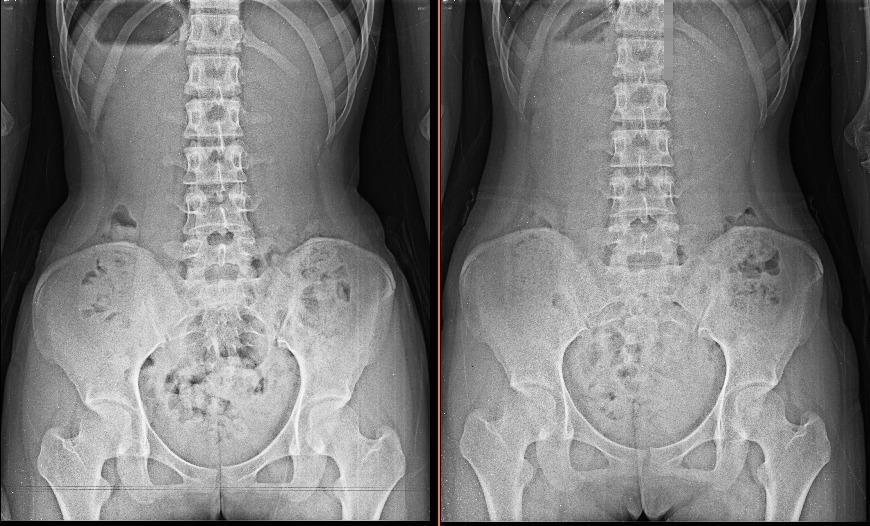

19세 여학생 골반교정사례입니다.

• 작성자MEMPT학회장 | 작성시간 12.04.02 요추 body rotation 이 좋아 젔내요,,보기 좋아요,,,

• 작성자신승용(총무이사) | 작성시간 12.04.03 pelvic cavity의 모양도 예뻐졌네요 ^ ^